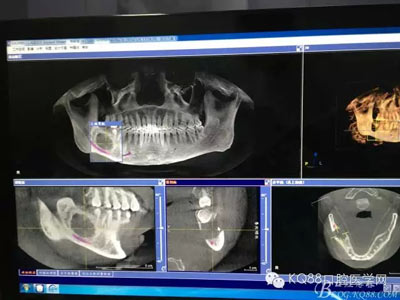

患者、常xx、男、26歲,主訴:右側(cè)下頜牙床腫痛不適數(shù)月。??茩z查:48未見萌出,頰側(cè)骨質(zhì)略有膨隆。捫診輕微不適,無乒乓感,牙齦色澤基本正常,探針無盲袋。全景片檢查:48埋伏水平阻生,其牙冠下方有一囊性陰影,界限清楚,大小約1.5x1.1cm。CBCT檢查:囊性病變已經(jīng)導(dǎo)致部分頰舌側(cè)骨板缺失。診斷:48埋伏阻生伴發(fā)囊性變。治療計劃:建議拔除48,并摘除下方的囊腫?;颊咄庵委熡媱?,簽知情同意書。

圖2.術(shù)前的CBCT檢查:48下方頜骨橢圓形囊性陰影,下方接近下頜管。